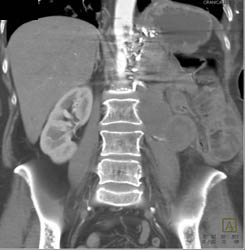

GSW Pelvis With Bleed